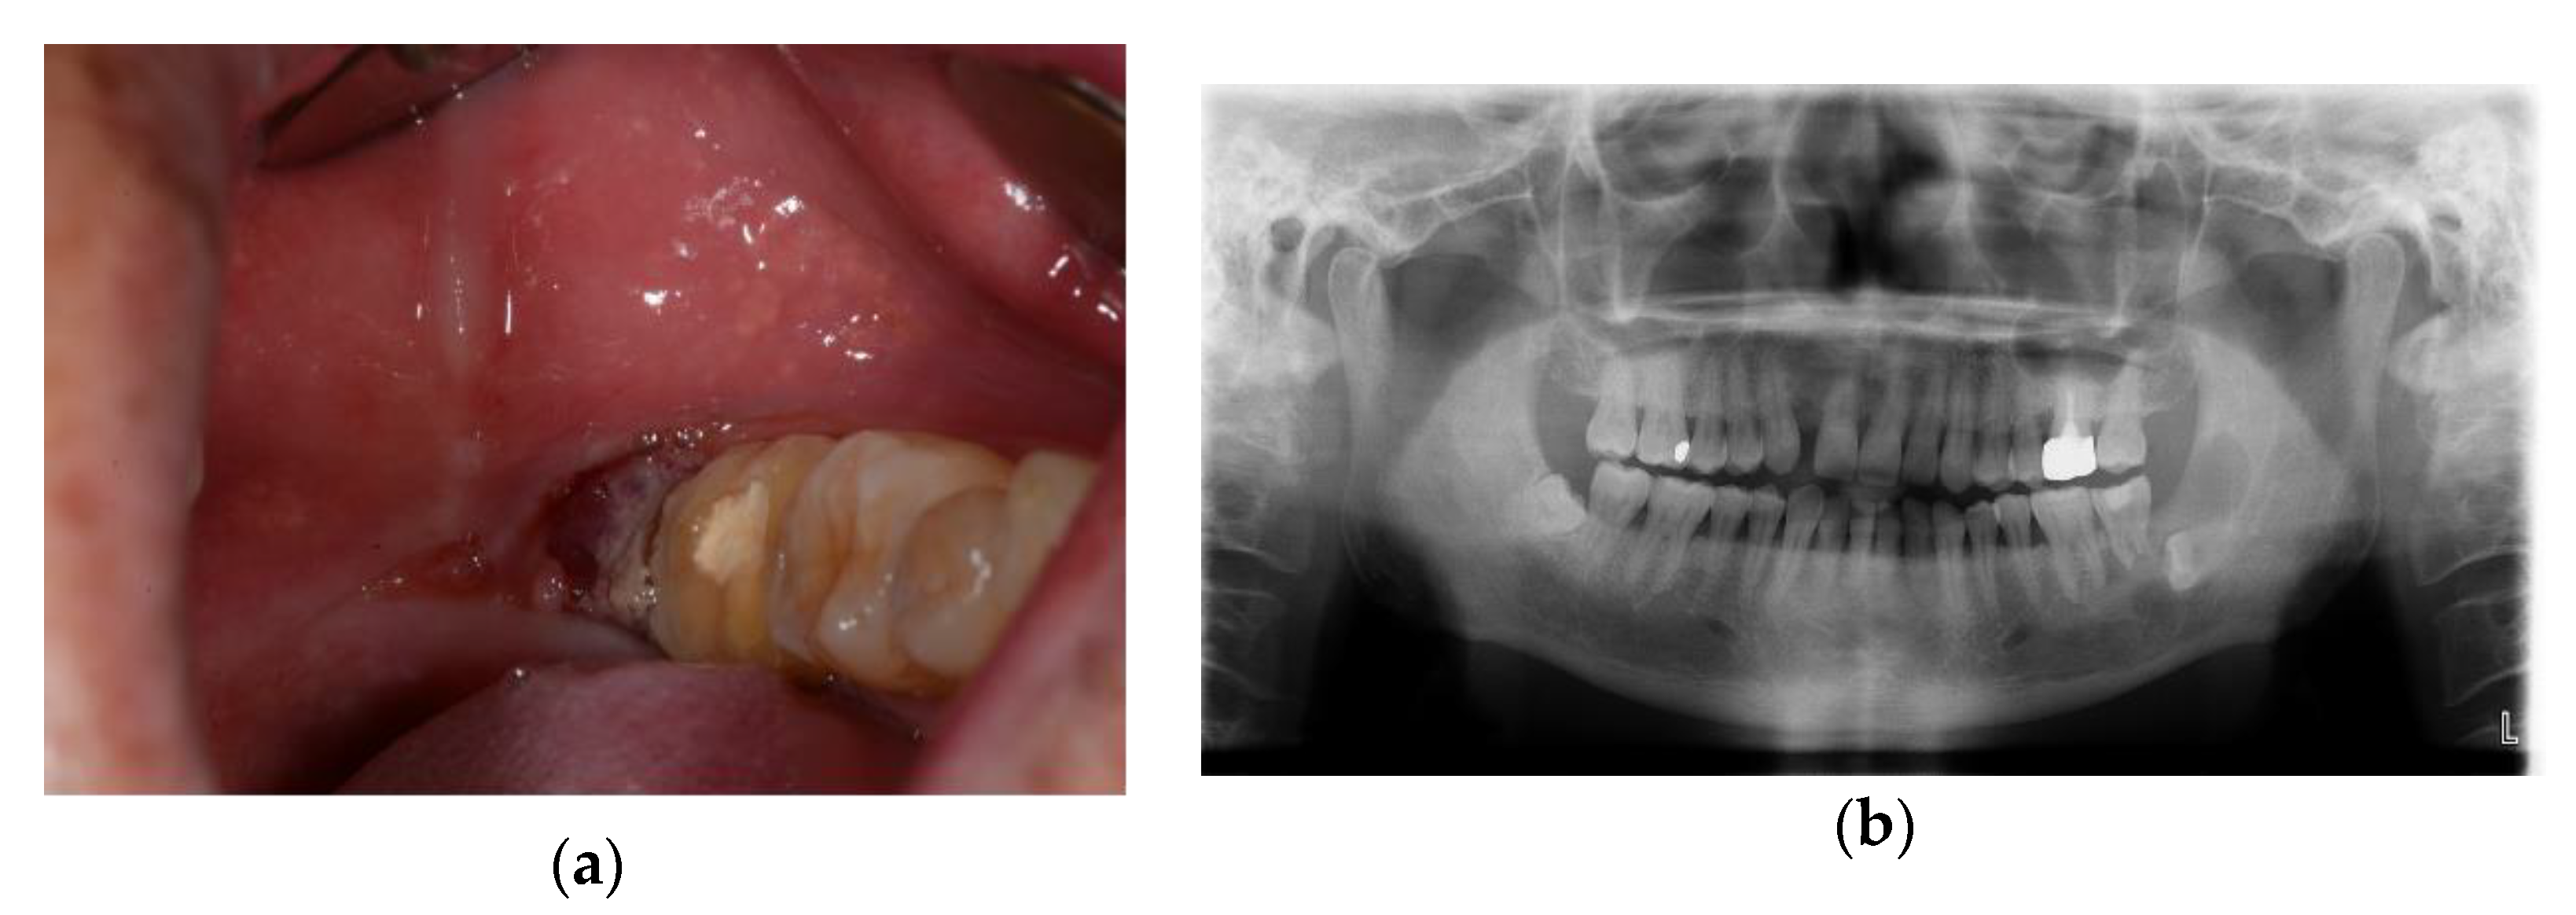

2.3. Case 3: Verrucous Carcinoma on Right Upper Gingiva

Conservative Treatment of Avulsion Fracture